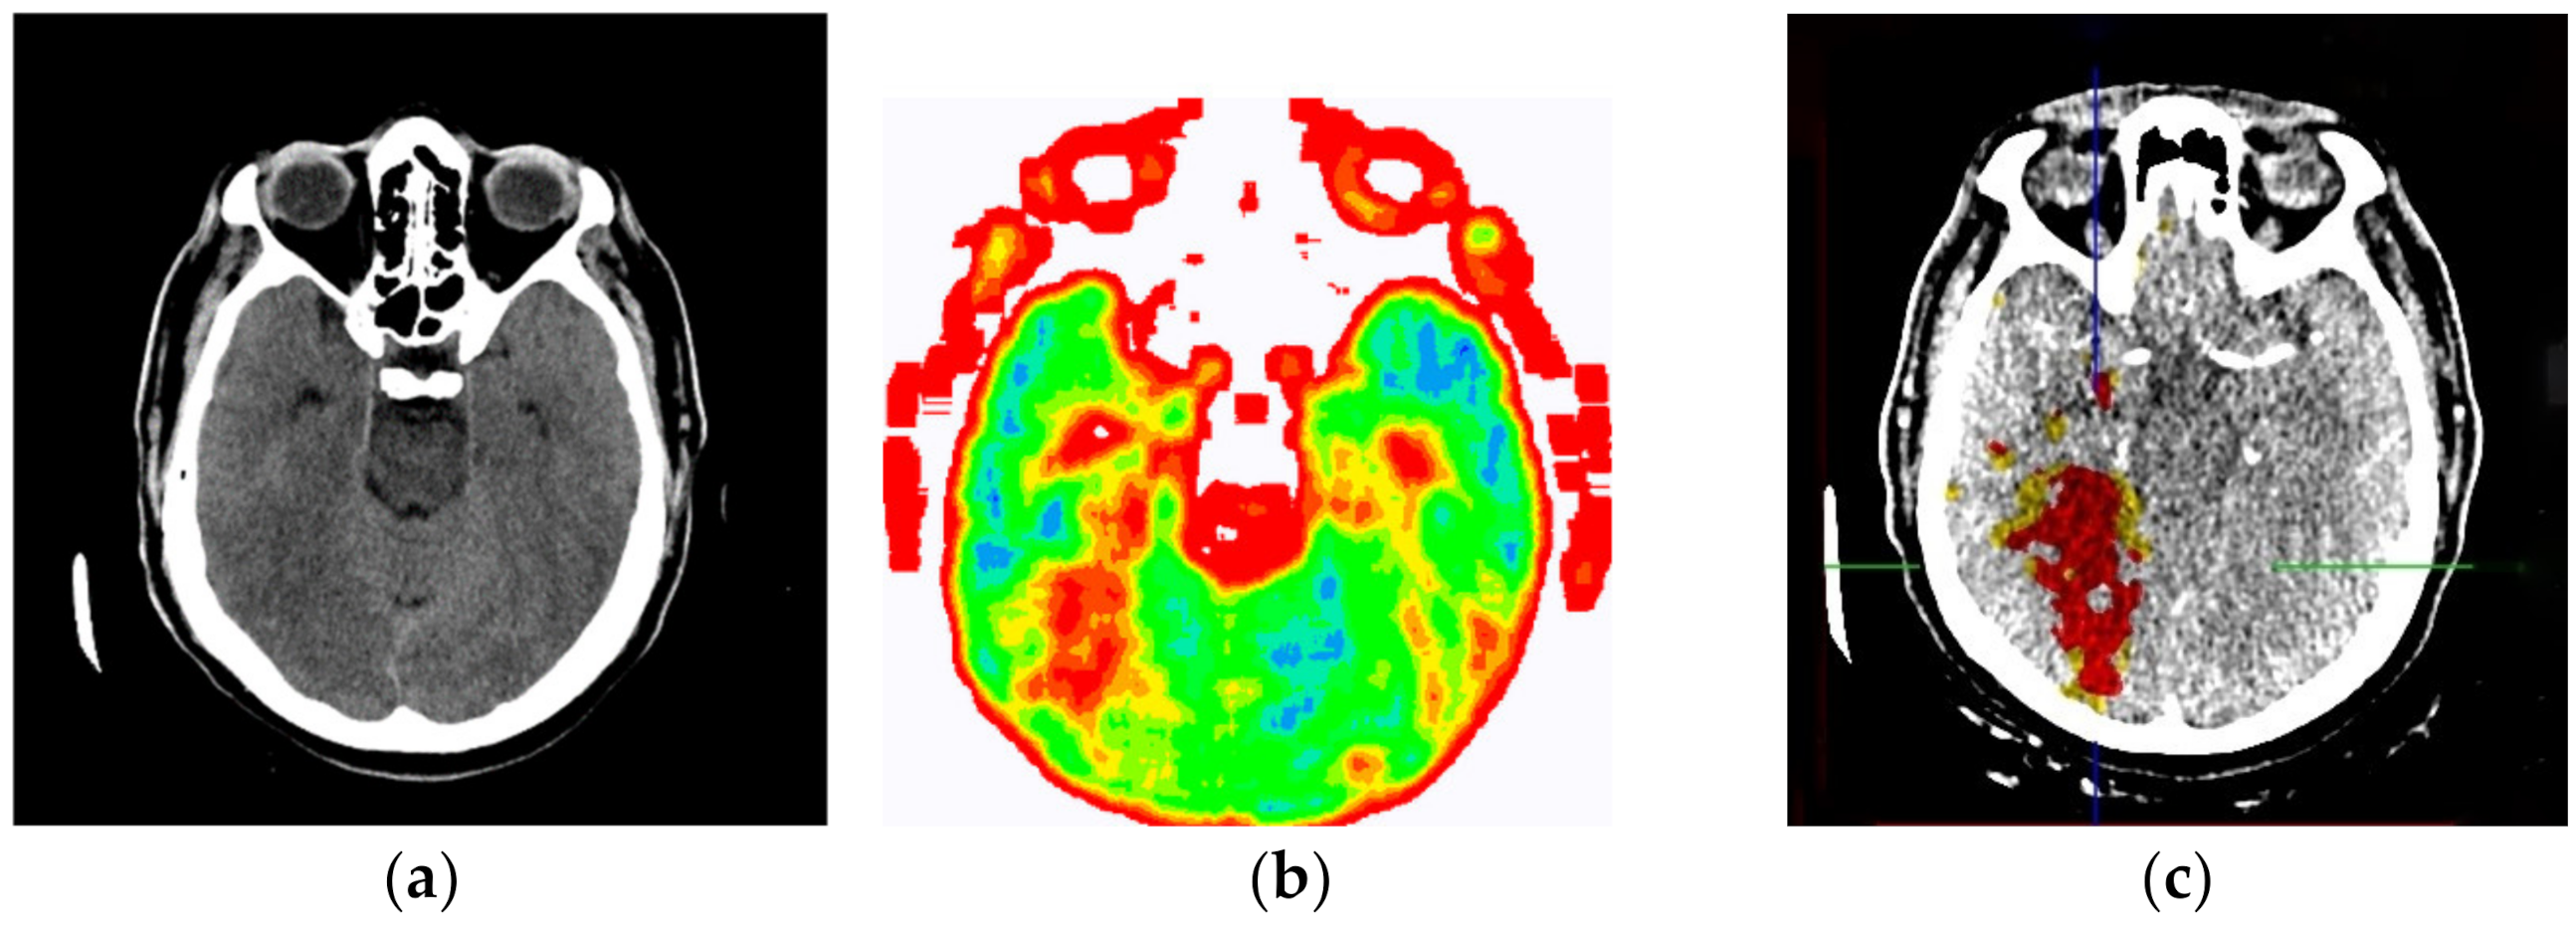

2.2. Smart Visualization Method (SVMI)

3.1. Technological Description

3.2. Evaluation of the Developed SVMI Model